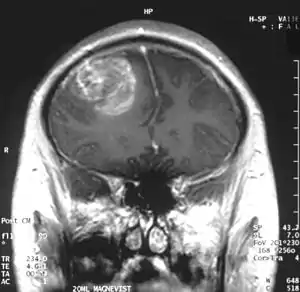

Somasundaram's work is centered around the studies of oncoviruses, tumor suppressor genes, gliomas and microRNAs and he has done advanced research on glioblastoma, an aggressive form of cancer affecting the brain.[8][9] The group led by him is engaged in work concerning the determination of the role of cellular tumor antigen p53 in glioma, regulating the protein, p73 in cervical cancer patients, using Adenovirus early region 1A, a tumor suppressor gene, the analytical study of BRCA1 gene in breast cancer and the analysis and regulation of SV2A, a synaptic vesicle protein.[3] He demonstrated that glioblastoma spreads rapidly by producing macrophage colony-stimulating factor (MCSF) in large quantities which in turn stimulate the growth of blood vessels in the tumor.[10] He proposed that the MCSF interacted with the anti-tumor microglial cells of the human body and induced them to produce Insulin-like growth factor-binding protein 1 (IGFBP1), thereby impairing the capacity of microglial cells to fight the tumor cells, a process he called befriending. The discovery of this new molecule, IGFBP1 and its role in glioma angiogenesis, led to a collaborative investigation which involved four research institutions namely National Institute of Mental Health and Neuro Sciences, Sri Sathya Sai Institute of Higher Medical Sciences and Institute for Functional Genomics (INSERM) of the University of Montpellier, apart from the IISc.[11] The research team led by Somasundaram and Phillipe Marin of INSERM validated the earlier findings and proposed a new therapeutic protocol for glioblastoma which targeted IGFBP1, rather than Vascular endothelial growth factor (VEGF) which earlier treatment methods attacked.[12] The researchers, later, released their findings through a paper, Glioblastoma-derived Macrophage Colony Stimulating Factor (MCSF) Induces Microglial Release of Insulin-like Growth Factor-Binding Protein 1 (IGFBP1) to Promote Angiogenesis, published in the Journal of Biological Chemistry.[13] Work is in progress at his laboratory for developing biomarkers (twenty genes of which is named gene X, have already been discovered)[14] for which detailed study is being conducted on microRNA, DNA methylation, modifications of chromatin and gene fusions.[4][15] His studies have been documented by way of a number of articles[16][17][note 1] and ResearchGate, an online repository of scientific articles has listed 178 of them.[18] He has also conducted workshops[19][20][21] including the Workshop on Next Generation Sequencing organized by the Council of Scientific and Industrial Research in November 2013[22] and has delivered invited or plenary speeches at various conferences and seminars[23] and the 5th annual meeting of the Proteomics Society, India held in September 2013 was one among them.[24]